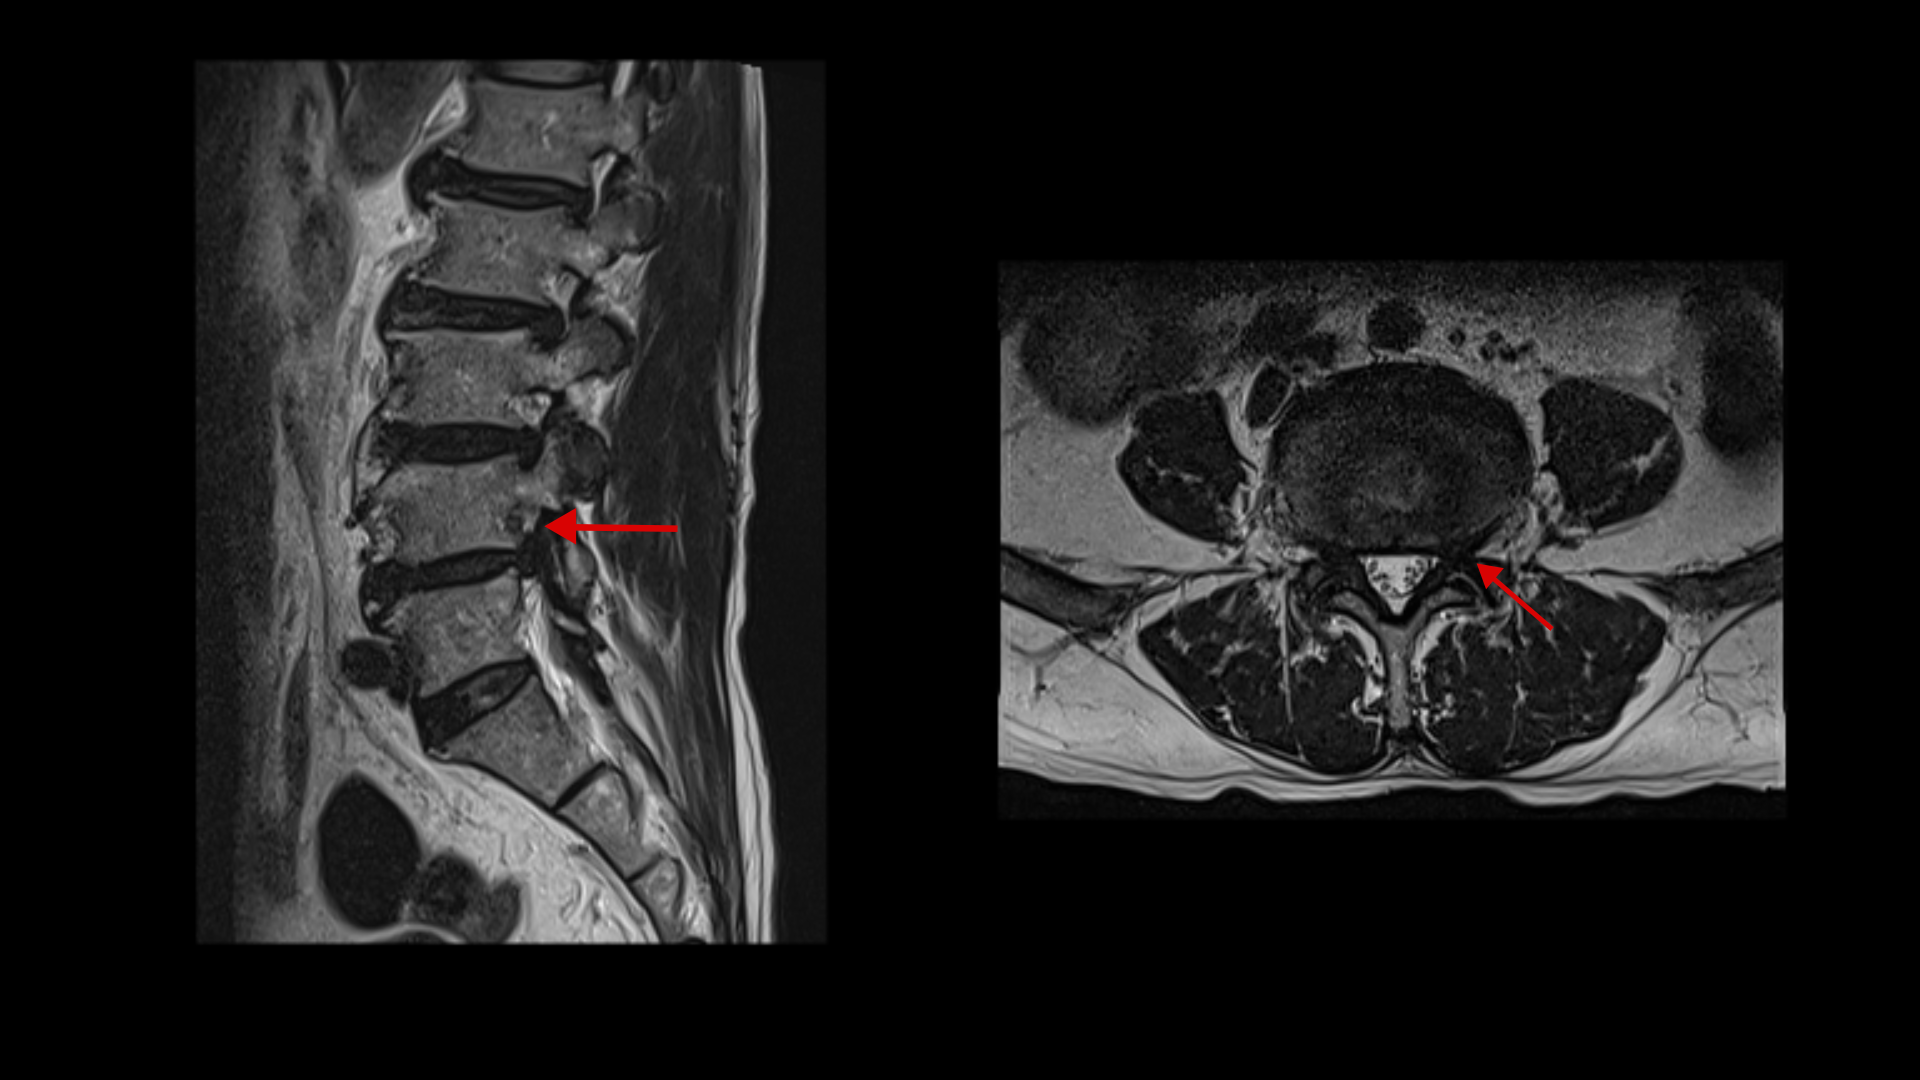

이 환자분은 두 달 전쯤 갑자기 허리가 아프면서 왼쪽 다리에 방사통이 생기면서 발목에 마비 증상이 발생했습니다. MRI를 보면 허리의 여러 마디에 퇴행성 디스크 및 디스크 탈출이 있고 특히 3번 4번과 4번 5번 마디에는 척추관협착증이 있습니다.

MRI를 다시 보면 4번 5번 마디에서 왼쪽으로 나가는 신경구멍이 밀려나온 디스크와 협착으로 인해 좁아져 있습니다. 다리마비와 방사통은 이것 때문에 발생한 증상으로 보입니다.